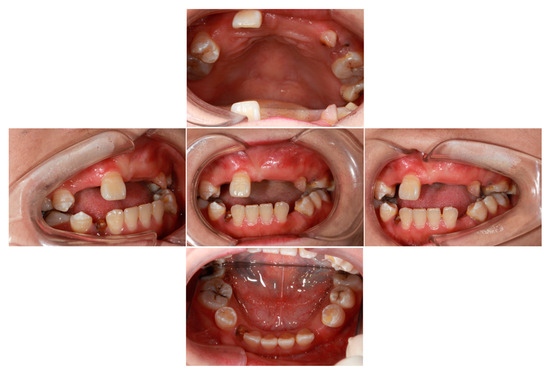

2.1. Clinical Features of Proband

2.2. Biochemical and Radiographic Analysis